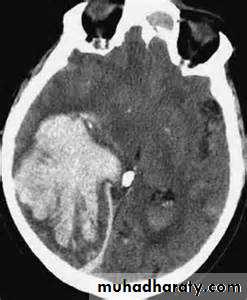

the principle imaging for ICH is CT scanning

Conventional T1 and T2 sequences are not highly sensitive to hemorrhage in the first few hours, but newer gradient refocused echo sequences appear to be able to detect intracerebral hemorrhage reliably within the first 1-2 hours of onset (MRI studies incorporating gradient echo or susceptibility-weighted sequences may be used as the sole imaging modality for patients with acute stroke, readily identifying intracranial hemorrhage• Vessel imaging